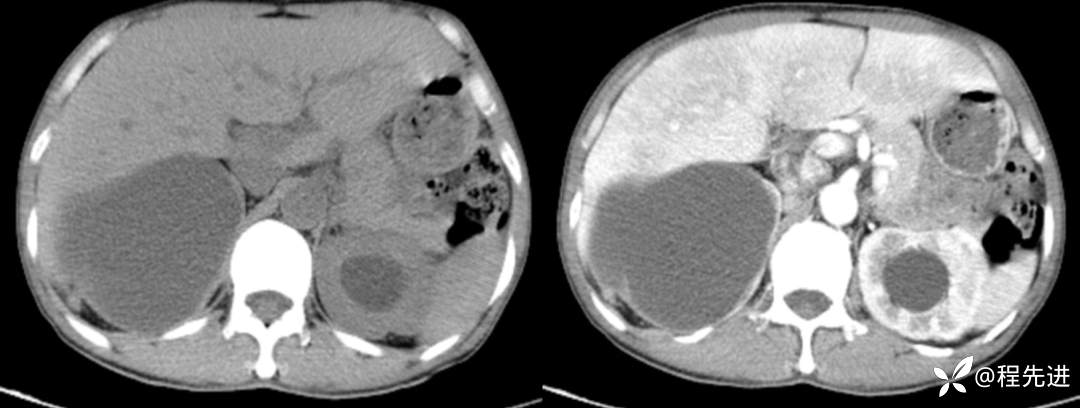

CT平扫+增强

左平扫,右增强

来张特定(左平扫,中动脉期,右静脉期)